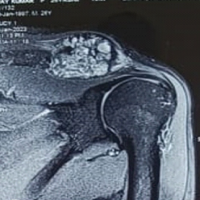

A 21-year-old female patient complained of deformity of both feet since her childhood associated with pain. The patient had undergone conservative modalities, such as orthotics, medical treatments, and insoles. The patient took physiotherapy with lifestyle modifications but had no pain relief. The patient felt that her feet were esthetically unpleasing (Fig. 1a and b). The patient was clinically evaluated and had shortening of bilateral fourth toes (Fig. 1a and b), tenderness over the bilateral fourth metatarsal ray, cock-up deformity over bilateral fourth toes, and sulcus sign over the plantar aspect of bilateral fourth toes. The patient had no comorbidities. The patient was evaluated for any associated syndromes and found to be negative. Pre-operative blood investigations and anesthesia fitness for surgery were obtained. A pre-operative plan was made using a bilateral foot X-ray. Anteroposterior and oblique views showed a 2-cm shortening in both fourth metatarsals (Fig. 2a, b) and a 5-mm shortening of the bilateral proximal phalanx (Fig. 2a, b) and malalignment of the Lelièvre parabolic arch[10] (Fig. 2c). A diagnosis of congenital bilateral brachymetatarsia of the fourth metatarsal was made. The patient was planned for lengthening of bilateral metatarsals using distraction osteogenesis with an external rail fixator[11,12].